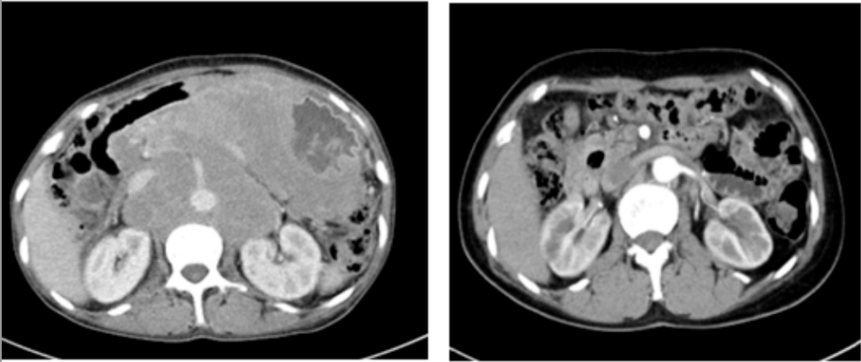

两年前,张阿姨(化名)的生活被一场突如其来的疾病打乱。持续地恶心、呕吐,整整一个月几乎未进食。在家人的陪伴下,来到国文医院进行全面检查。胃镜结果和腹部CT带来了一个沉重的消息:胃部弥漫大B细胞淋巴瘤,并且已形成一个直径约10厘米的巨大包块。这不仅仅是一个肿瘤,更是一枚“不定时炸弹”。因为淋巴瘤的侵犯,张阿姨的胃壁已经形成了巨大溃疡,随时可能引发消化道大出血或穿孔,性命危在旦夕。

精密的策略迎来了胜利的曙光,四周期治疗后复查胃镜,原有的巨大溃疡已完全消失。肿瘤得到有效控制,穿孔风险解除!在此基础上,后续的四个周期治疗调整为标准的R-CHOP方案,乘胜追击,力求彻底清除病灶。

历经八个周期的规范化疗,最终的评估结果让所有人欢欣鼓舞:张阿姨的病情在影像学检查上显示肿瘤已消失。